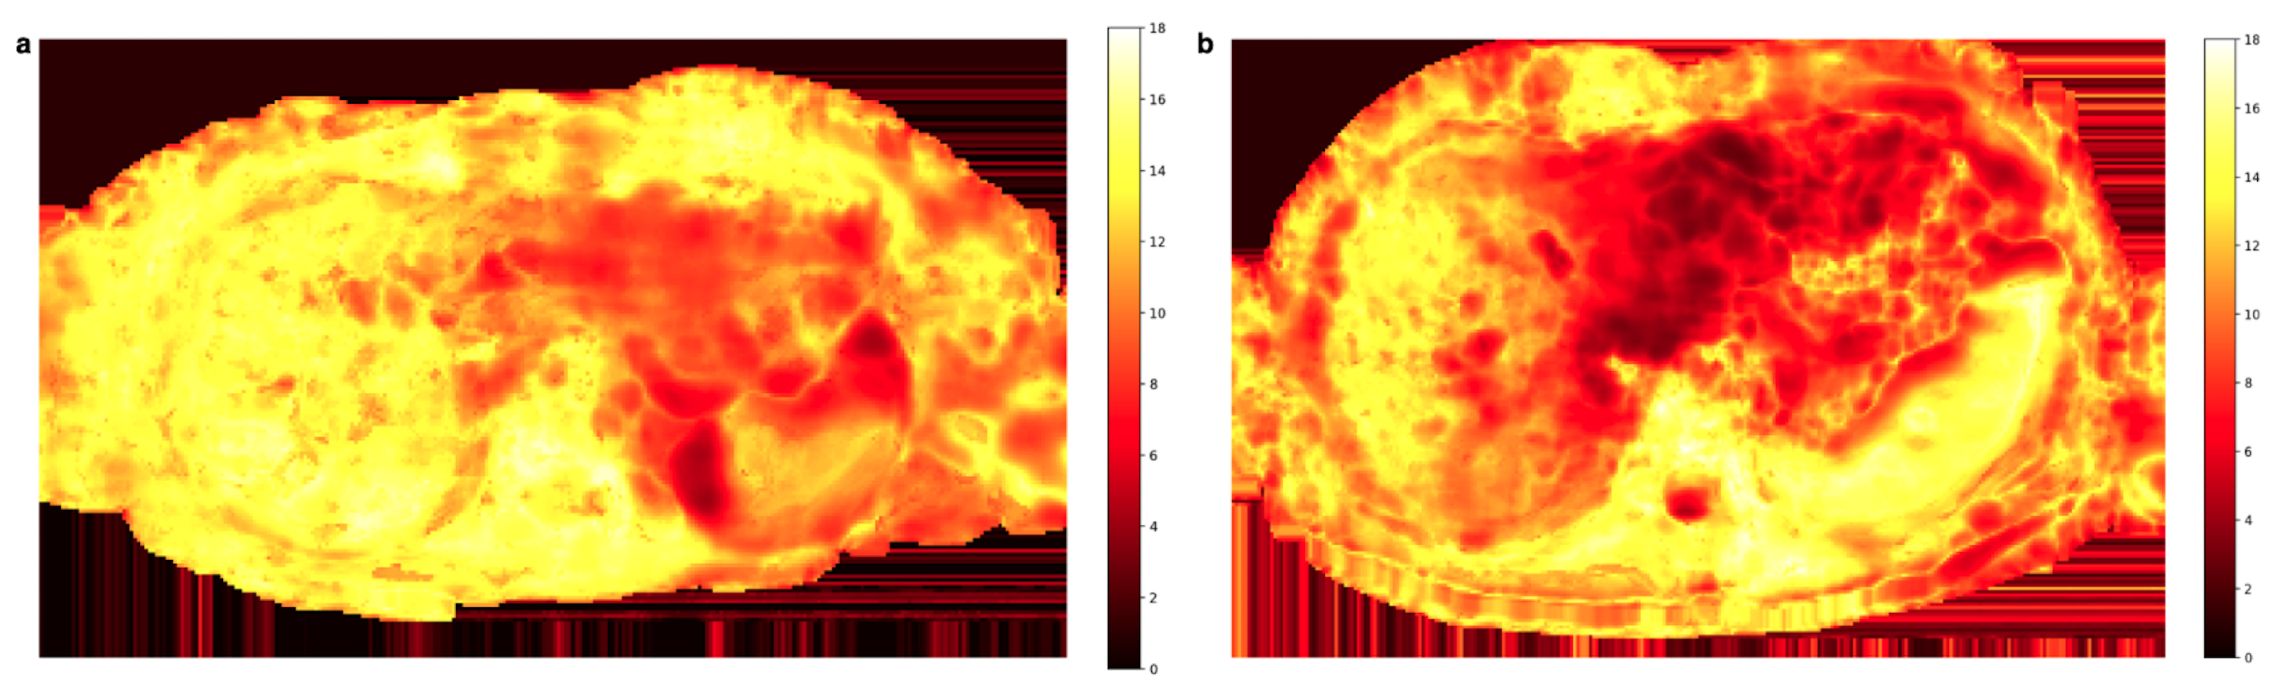

3.2. Spatial Scaling of Average DWI

3.3. Quantitative ADC Measurement